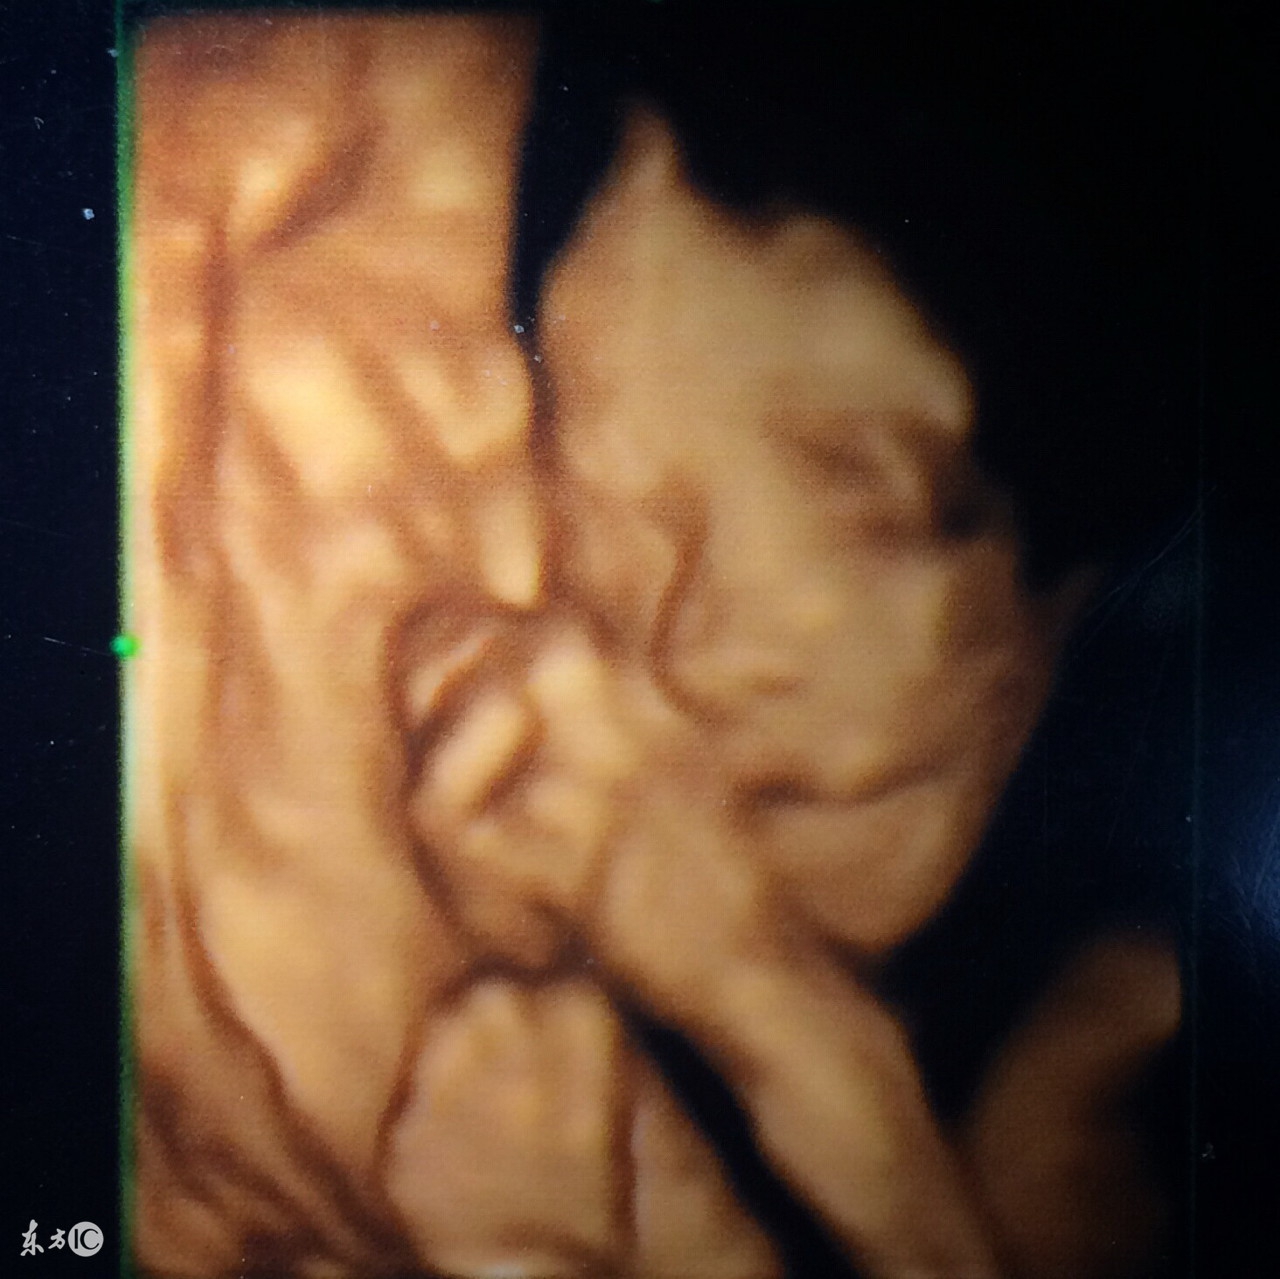

6、四维彩超:可能是土黄色,录像,动态,能够刻录成光盘,有排畸作用;

图片来源于百度图片

3、四维彩超

四维彩超也称大排畸检查,做四维彩超的最佳时间是在24-28周,这时宫内空间大,宝宝活动方便,回声比较小,图像会更加清楚。